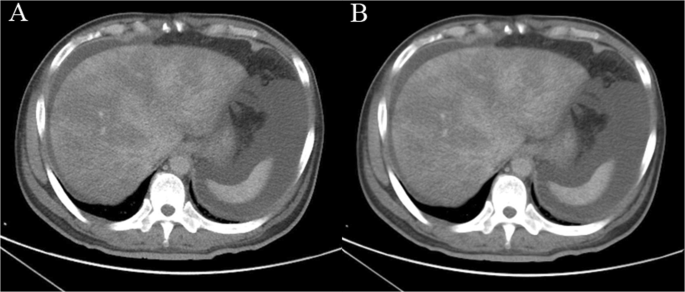

Liver extraction and measurement without denoising are difficult because the intensity distribution of the liver is irregular due to noise23. The anisotropic diffusion method can reduce the effect of noise while preserving the boundaries and fine details of organs and tissues on a CT image. The parameters of the anisotropic diffusion method were as follows: iterations = 4 and time step = 0.125. CT images of patients with PA-SOS were denoised through an anisotropic diffusion filter24 (Fig. 2).

(A) 49-year-old man was diagnosed with PA-SOS and underwent contrast-enhanced CT. CT images were denoised using the anisotropic diffusion method; (A) original and (B) denoised.